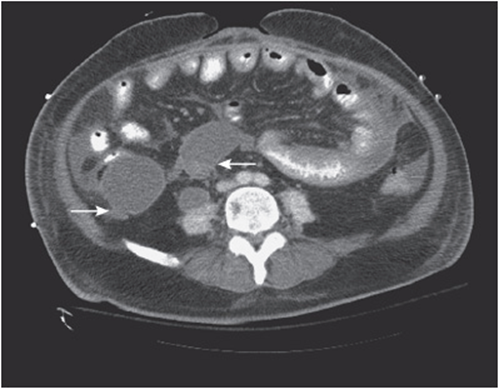

viii. Check for tumors, inflammation, ductal dilatation, and/or intraductal stones (see Figure 56-7). Check the kidneys for hydronephrosis, lacerations, or pericapsular hematoma (see Figure 56-8).

Figure 56-7. Severe pancreatic inflammation.

Figure 56-8. Left kidney hematoma caused by a motor vehicle crash.